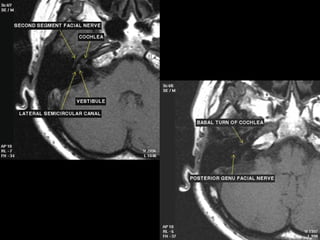

 Intratemporal facial nerv;

CN7 segments: lAC, labyrinthine, tympanic, mastoid segments

Geniculate ganglion = anterior genu

Posterior genu: Tympanic segment bends inferiorly to become mastoid

segment

Facial nerve

 The facial nerve is one of the key cranial nerves with a complex and broad range of

functions.

 Although at first glance it is the motor nerve of facial expression which begins as a trunk

and emerges from the parotid gland as five branches it has taste and parasympathetic

fibres that relay in a complex manner.

 The facial nerve is the only cranial nerve that may show normal post-contrast

enhancement, although this applies only to the labyrinthine segment up to

the stylomastoid foramen. Enhancement of the other segments of the facial nerve and

other cranial nerves is considered pathologic.

Segments

 intracranial (cisternal) segment - zero branches

 meatal (canalicular) segment (internal auditory canal): 8 mm long, zero branches

 labyrinthine segment (IAC to geniculate ganglion): 3-4 mm long, 3 branches

(from geniculate ganglion)

 tympanic segment (from geniculate ganglion to pyramidal eminence): 8-11 mm

long, zero branches

 mastoid segment (from pyramidal eminence to stylomastoid foramen): 8-14 mm long, 3

branches

 extratemporal segment (from stylomastoid foramen to division into major branches): 15-

20 mm, 9 branches